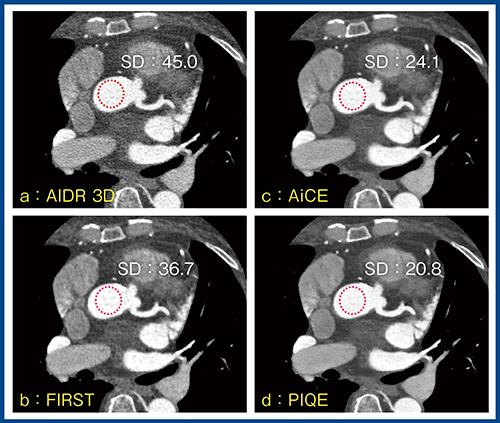

図9はBMI 38.7の高体重症例である。相対的に線量不足となっているが,PIQE(d)では画質が著明に改善し,SDもAIDR 3D(a)の45.0HUに対し,20.8HUまで低下している。冠動脈のcurved MPRにおいても,PIQEでは画質が大きく改善し,読影に耐えうる画像であった。

図9 高体重症例(BMI 38.7)における画質改善